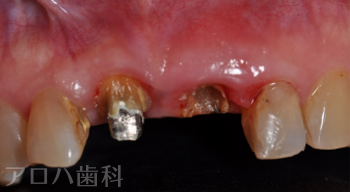

初診時

| 主訴 | 左の前歯が折れた |

| 治療内容 | 左上前歯にお痛みがあり、土台を外したところ、破折により抜歯となった方です。 骨が薄かったため、抜歯と同時にインプラントを行う【抜歯即時インプラント】を行いました。 インプラント治療により歯があったときと変わらない状態に回復しました。 |

| 治療期間 | 1週間 |

| 治療費用 | 627,000円 |

| 費用詳細 | ・TEC 22,000円 ・サージカルガイド 55,000円 ・GBR 110,000円 ・インプラント手術+アバットメント+上部構造 440,000円 |